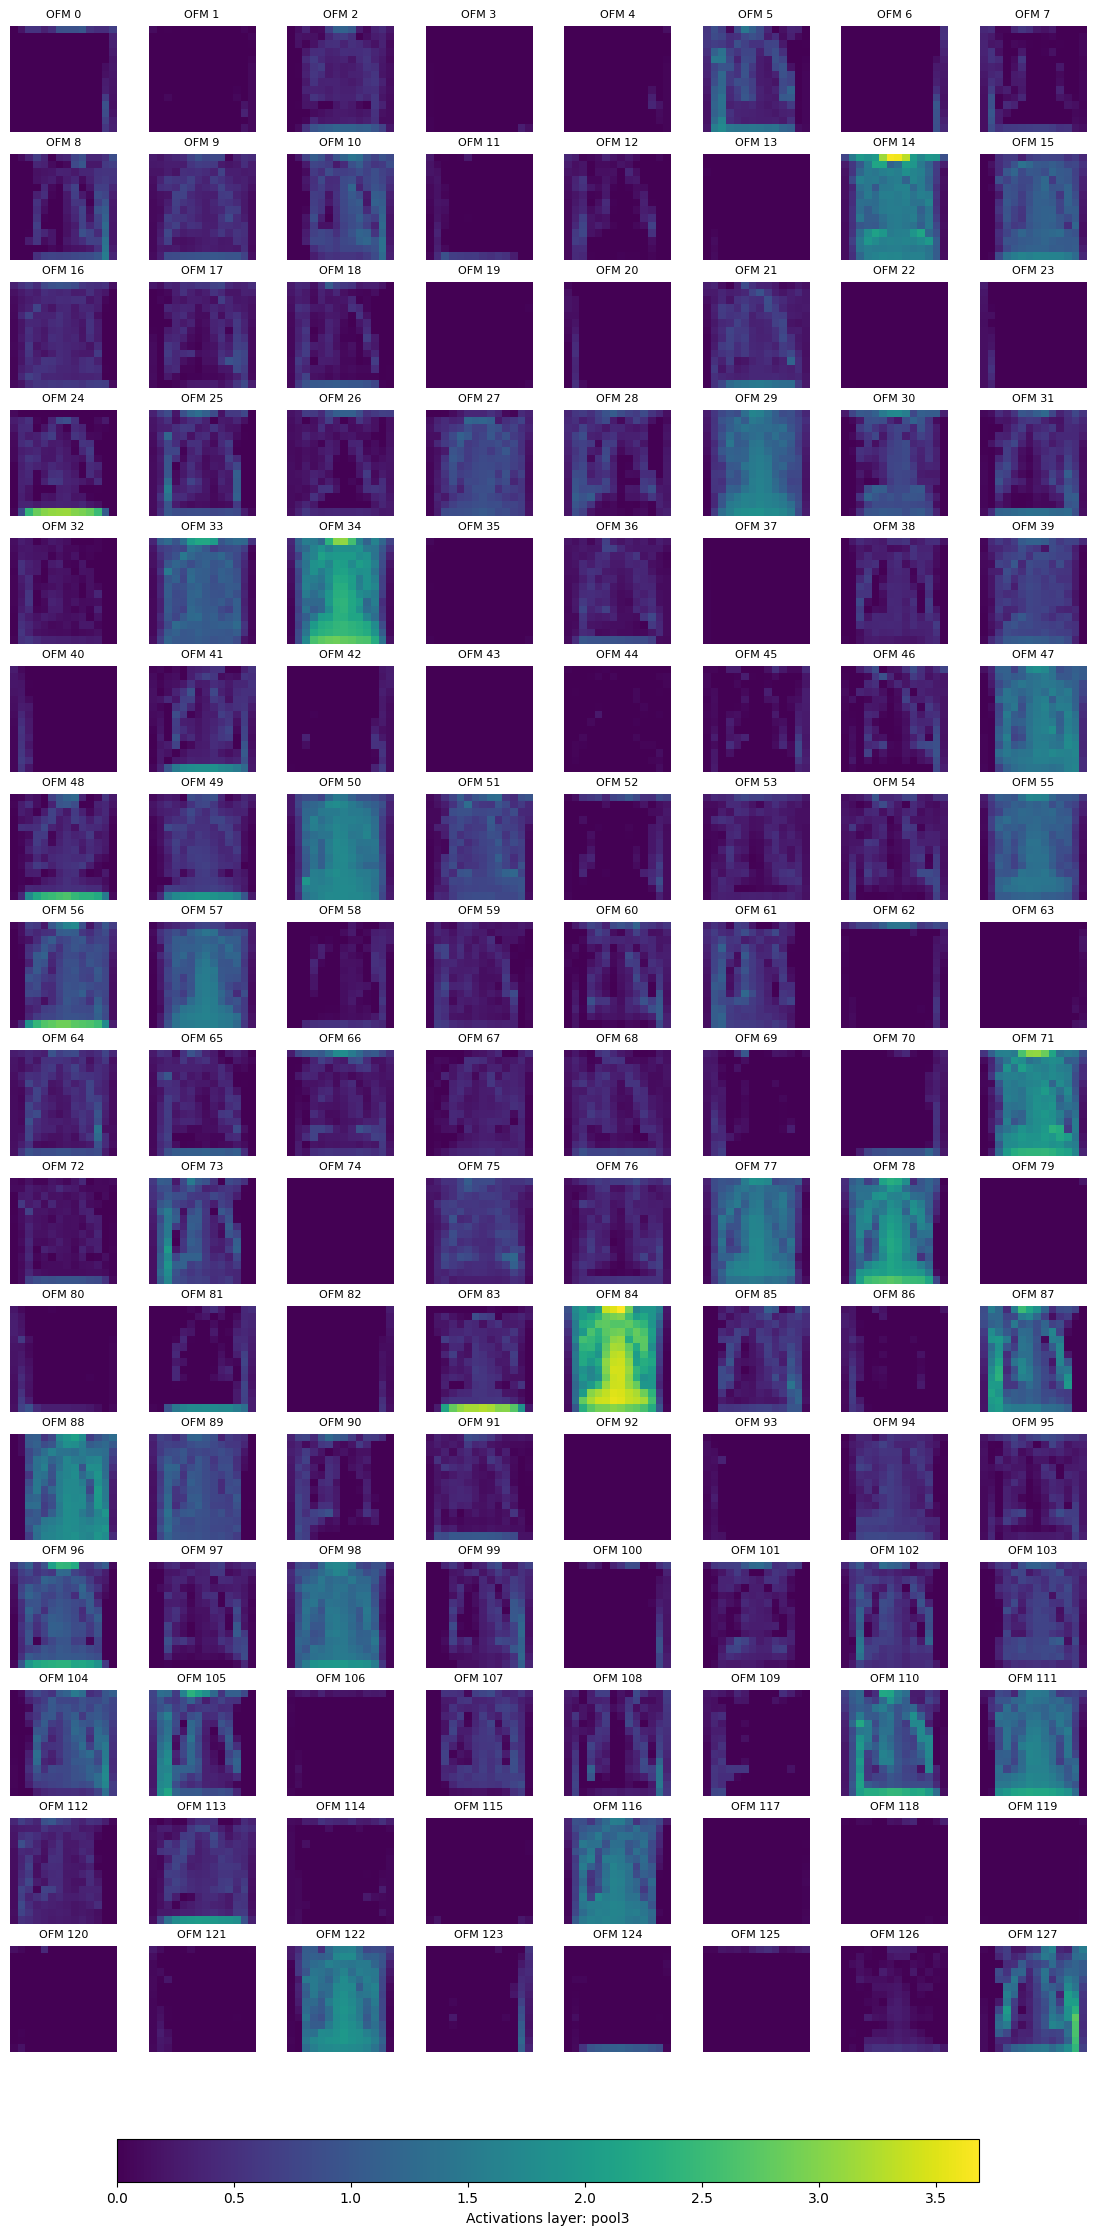

We can also plot the activations (output feature map) after the pool layer, for pool2 and pool3.

for k, activation in activation_cnn.items():

if k in ['pool1', 'pool4']:

continue

nrows, ncols = (4*activation.shape[0]//32, 8)

fig, axs = plt.subplots(nrows, ncols, figsize=(14, 7 * nrows//4))

print(f'Displaying layer: {k}, shape: {list(activation.shape)}, number of output feature maps (OFM): {activation.shape[0]}\n')

max_val = torch.max(activation)

for ch in range(activation.shape[0]):

r, c = (ch//8), ch%8

im = axs[r, c].imshow(activation[ch].cpu().numpy(), cmap='viridis', vmin=0, vmax=max_val)

axs[r, c].set_title(f'OFM {str(ch)}', fontsize = 8)

axs[r, c].axis('off')

cbar = fig.colorbar(im, ax=axs, orientation='horizontal', fraction=0.02, pad=0.04)

cbar.set_label(f'Activations layer: {k}')

plt.show()

Displaying layer: pool2, shape: [64, 28, 28], number of output feature maps (OFM): 64

../_images/b007895c5a8024d841fad3727b481afeb746c6b5fa6042f928502ed66270c69a.png

Displaying layer: pool3, shape: [128, 14, 14], number of output feature maps (OFM): 128

../_images/d872ec62e00139de23f3961f3f60f8e5e5a779d636d109eb81134cc8e92af557.png